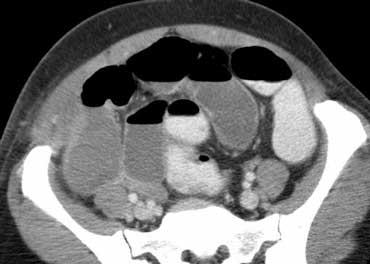

Siêu âm điển hình cho thấy dày thành dưới niêm mạc (đầu mũi tên) của hồi tràng đoạn cuối và manh tràng mà không có viêm mỡ xung quanh.

Viêm hồi manh tràng do vi khuẩn

Viêm ruột nhiễm khuẩn có thể gây ra các triệu chứng nhẹ giống viêm dạ dày ruột do virus thông thường, nhưng cũng có thể biểu hiện lâm sàng với các đặc điểm không thể phân biệt được với viêm ruột thừa, đặc biệt trong viêm hồi manh tràng do vi khuẩn, gây ra bởi Yersinia, Campylobacter hoặc Salmonella.

Dấu hiệu chính: Dày thành hồi manh tràng không kèm viêm mỡ, hạch to, ruột thừa bình thường